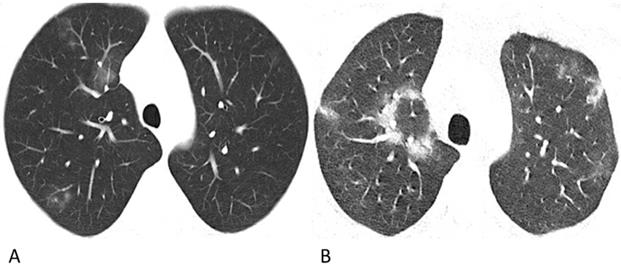

Figure 1

Representative chest CT images of COVID-19 pneumonia (A-C) and lymphoma-associated pneumonia (D-F). (A) A 62-year-old man who worked in Wuhan had a fever and chest tightness. Patchy GGOs are shown in more than one lobe. (B) A 42-year-old man, who was in close contact with a confirmed patient developed fever and cough on admission. Patchy GGOs in the peripheral right lung and mixed GGOs in the left lung are observed. Bronchograms are shown in the lesions. (C) A 28-year-old man who was in close contact with the confirmed patient in Fig. 1A developed fever. A single mixed GGO and consolidation is shown in the left lung. Focal interlobular septal thickening could be observed. (D) A 61-year-old man was diagnosed with ALK (+) anaplastic large cell lymphoma and received chemotherapy with CHOP before chest CT, and he did not have a fever or a positive epidemiological history. Diffuse patchy GGOs are shown in more than one lobe. (E) A 49-year-old man was diagnosed with diffuse large B-cell lymphoma, and received chemotherapy with rituximab before the chest CT. He had a fever during chemotherapy but had no epidemiological history of COVID-19. Diffuse patchy GGOs with several solid nodules are shown in both upper lobes. (F) A 69-year-old man was diagnosed with diffuse large B-cell lymphoma, and received chemotherapy with rituximab before the chest CT, and he did not have a fever or a positive epidemiological history. Slightly diffuse patchy GGOs are shown in the left upper lobe, and patchy consolidation was observed in the right upper lobe.

As shown in Table 3, no significant differences in the number of affected lobes (p = 0.481) or location (p = 0.186) were observed between the COVID-19 group and lymphoma group. The proportion of patchy lesions in the COVID-19 group and lymphoma group was 84% (94/112) and 83% (62/75), respectively (p = 0.843). For patchy lesions, the COVID-19 patients and lymphoma patients had the following distribution of lesion densities: GGO, 55% (52/94) versus 42% (26/62); mixed GGO and consolidation, 44% (41/94) versus 50% (31/62); and consolidation, 1% (1/94) versus 8% (5/62) (p = 0.036). For nodular lesions, the COVID-19 patients and lymphoma patients had the following distribution of lesion densities: GGO, 39% (7/18) versus 0% (0/13); mixed GGO and consolidation, 44% (8/18) versus 23% (3/13); and consolidation, 17% (3/18) versus 77% (10/13) (p = 0.002). Regarding the diffusion degree, 82% (92/112) of the COVID-19 group lesions were relatively limited, while 69% (52/75) of the lymphoma group lesions were diffuse (p < 0.001) (Figure 1).

However, for lymphoma patients with pneumonia, solid nodules occupied 77% in nodular lesions, while for COVID-19 patients, GGO and mixed GGO nodules occupied 83% (p = 0.002). Notably, compared with the lesions of COVID-19 patients which were relatively limited or confined, the lesions of lymphoma patients were much more diffuse in the lung, like the “diffuse mist” (p < 0.001) (Fig. 1). This may be a critical characteristic in identifying pneumonia associated with lymphoma from that associated with COVID-19. Furthermore, air bronchograms were seen less frequently in lymphoma patients with pneumonia than in COVID-19 patients (5% vs. 45%, p < 0.001). Additionally, no halo sign or reversed halo sign was observed in lymphoma patients with pneumonia. After antibiotic and symptomatic treatment, the patchy lesions on the follow-up CT of the lymphoma patient decreased (Fig. 3); therefore, the patient was able to tolerate continuous chemotherapy.